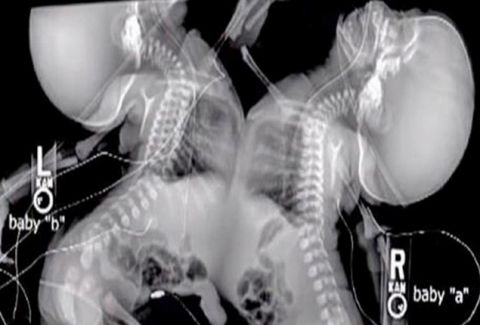

Τα δίδυμα ήταν ενωμένα στο στέρνο τους, στο διάφραγμα, στο συκώτι και στην μεμβράνη γύρω από την καρδιά. Ο φόβος ότι τα μικρά κορίτσια δεν θα επιβίωναν τον διαχωρισμό, οδήγησε τους γιατρούς να συμβουλέψουν την Shellie να τερματίσει την εγκυμοσύνη.

Όταν η Shellie Tucker ήταν 22 εβδομάδων έγκυος αντιμετώπισε μία έκπληξη. Της είπα ότι είναι έγκυος σε δίδυμα, αλλά ενωμένα δίδυμα.

Ο γιατρός που ήταν εξειδικευμένος σε εγκυμοσύνες υψηλού κινδύνου είπς στην Shellie ότι τα ενωμένα της δίδυμα ήταν πολύ απίθανο να επιβιώσουν μετά τον διαχωρισμό τους.

Η Shellie αποφάσισε λοιπόν να κρατήσει τα κοριτσάκια, την Allison και την Amelia. Μετά από μία δεύτερη γνώμη από το Παιδιατρικό Νοσοκομείο της Φιλαδέλφεια, βγήκε το πόρισμα ότι τα μικρά θα επιβίωναν τον διαχωρισμό.